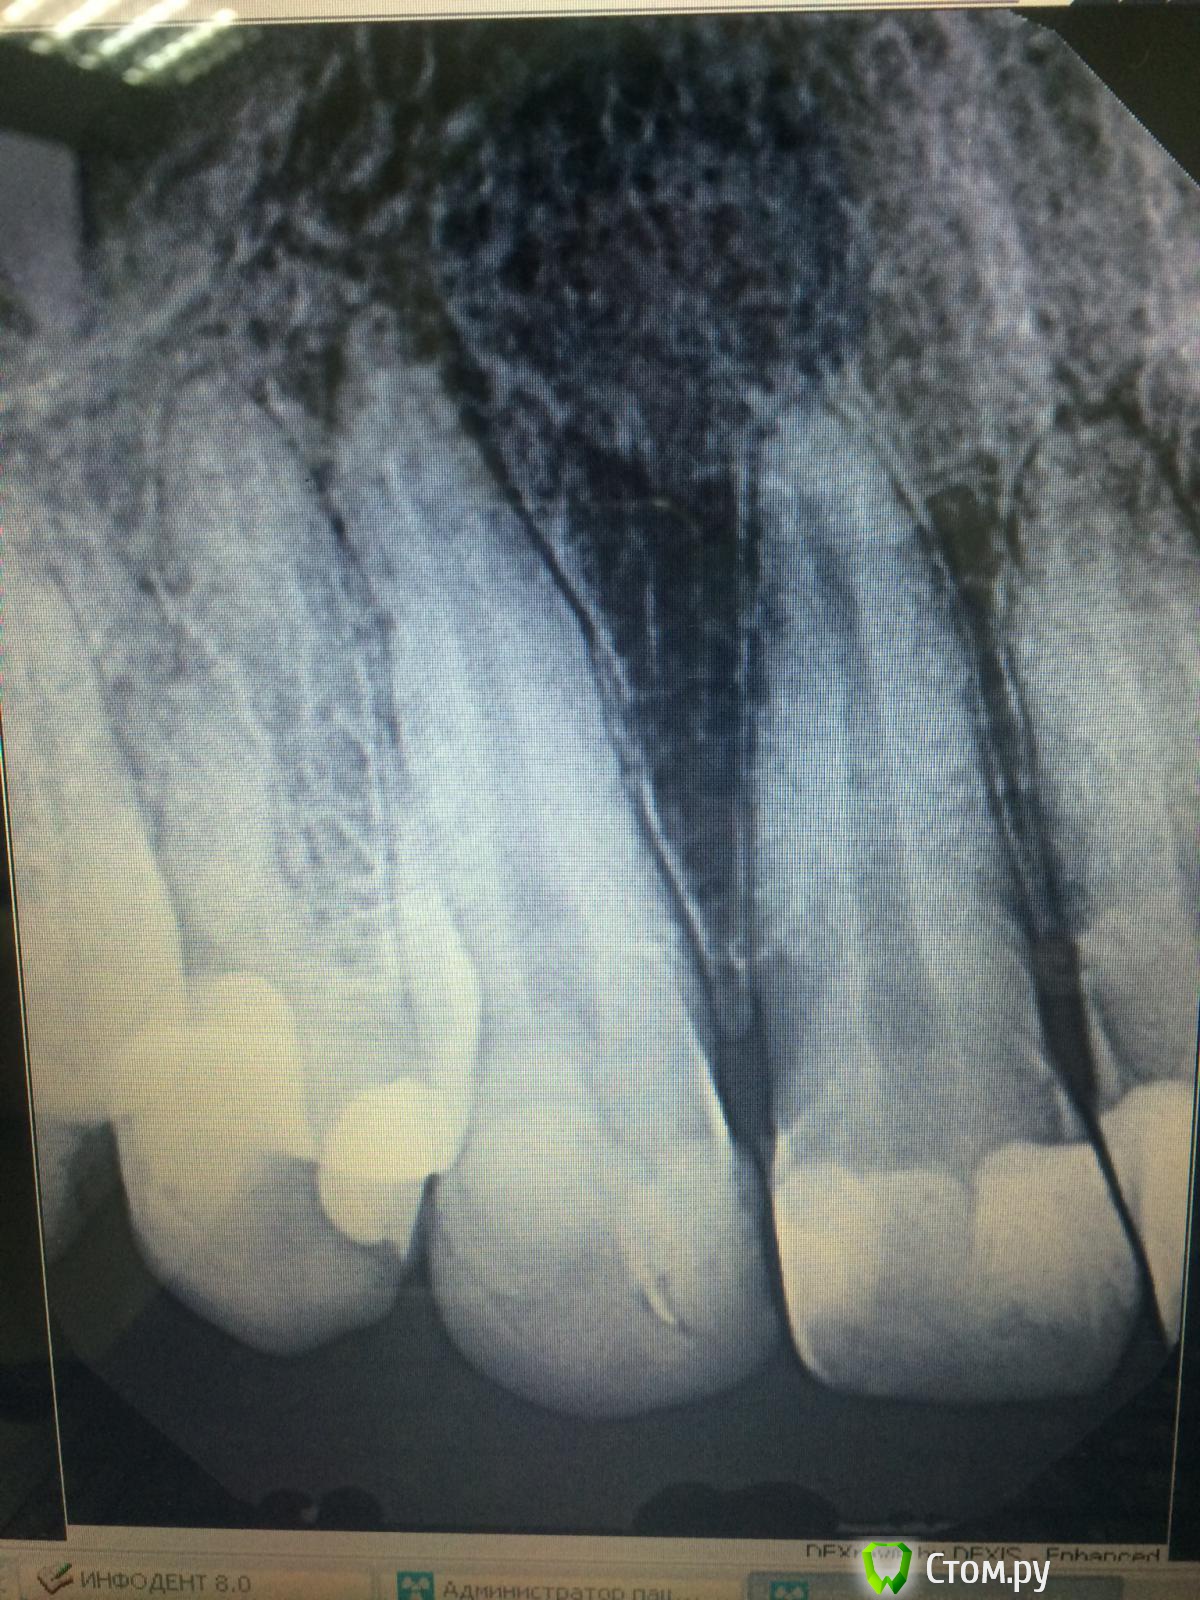

kspilnichenko Опубликовано 14 октября, 2014 Поделиться Опубликовано 14 октября, 2014 Уважаемые доктора,помогите определиться с тактикой лечения. Около месяца назад под инфильтрационной анестезией проведена замена пломб ( 13 зуб) на апроксимальных поверхностях и в пришеечной области,зуб виртуальный,полость зуба не вскрыта,до лечения жалоб не предъявлял. На след день пациент обратился с дискомфортом при жевании, после при шлифовки пломбы накусывать стало не больно. Но сейчас отмечает боли при надавливании в области верхушки,со слов "такое ощущение,что есть синяк" . При осмотре гематом нет,перкуссия безболезненна, термопроба отрицательна. Пальпация по пешеходной складке чувствительна,но ни гиперемии,ни отека нет. Подскажите,пожалуйста,что это может быть и что с этим делать? Грешила на анестезию, но беспокоит уже около месяца . Ссылка на комментарий

faity Опубликовано 14 октября, 2014 Поделиться Опубликовано 14 октября, 2014 как-то так Ссылка на комментарий

Андрей Боровой Опубликовано 16 октября, 2014 Поделиться Опубликовано 16 октября, 2014 пульпа погибла 100%=эндо Ссылка на комментарий